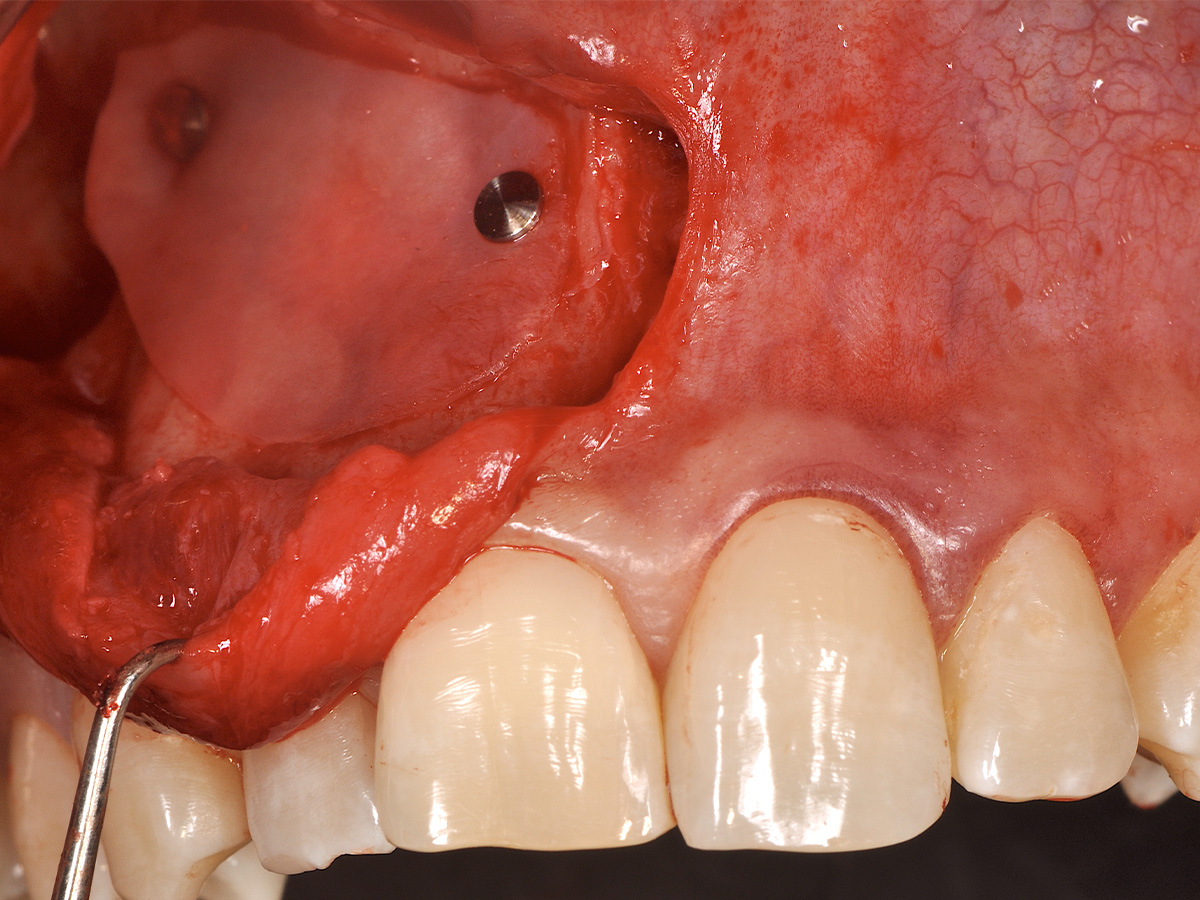

Abbildung 10

Nach vestibulärer Freilegung wurde die Zyste vollständig entfernt und zur histopathologischen Untersuchung eingesandt.

Mit der Patientin wurde der Versuch des Zahnerhaltes trotz ausgedehnter Zyste besprochen. Gleichzeitig sollte das Zystenlumen zu einer sicheren ossären Durchbauung geführt werden, um eine implantologische Sofortversorgung vorzubereiten, falls zu einem späteren Zeitpunkt eine Zahnentfernung notwendig werden sollte. In der Phase vor der geplanten Operation wurden die Wurzelkanalfüllungen an Zahn 11 und 12 durch einen Endodontologen alio loco revidiert. Die Schnittführung wurde aufgrund des bestehenden „Gummy Smile“ hoch im Vestibulum geführt – so konnte die delikate Parodontalstruktur in ihrer Form unangetastet belassen werden, um einen möglichst optimalen ästhetischen Erfolg zu erreichen (Abb. 8, 9). Nach vestibulärer Freilegung wurde die Zyste vollständig entfernt und zur histopathologischen Untersuchung eingesandt (Abb. 10). Anschließend erfolgte eine Wurzelspitzenresektion an den Zähnen 11 und 12 durch die vestibuläre ossäre Perforation (Abb. 11), gefolgt von einer ultraschallbasierten, retrograden Kanalaufbereitung und Abdichtung mit MTA. Um die knöcherne Durchbauung am Boden der Zyste osteoinduktiv zu unterstützen, wurden mit Hilfe eines mechanischen Knochenschabers aus dem Bereich des rechten naso-palatinalen Pfeilers Knochenchips entnommen und als erste basale Augmentationsschicht in den ossären Defekt eingebracht (Abb. 12). Der größere Anteil von 80 % des Defektvolumens wurde mit einem vollständig resorbierbaren, xenogenen Augmentationsmaterial aufgefüllt (Abb. 13) (mp3®, OsteoBiol®). Der Defekt wurde zum Vestibulum hin mit einer stabilen, vollständig degradierbaren Membran abgedeckt (Abb. 14) (Soft Cortical Lamina, OsteoBiol®). Zum einen wurde hiermit im Sinne der GBR das Weichgewebe vom Augmentat getrennt. Zum anderen verhinderte die stabile Membran das Einwachsen eines Weichgewebeankers in den Defekt und damit eine narbige Verziehung im Vestibulum. Um eine Verschiebung der Membran zu vermeiden, wurde diese mit zwei Titanpins in der Kortikalis fixiert. Die Pins wurden bei Beschwerdefreiheit in situ belassen (Titan-Bone-Pin-System). Der Wundverschluss erfolgte einschichtig mit nicht resorbierbarem Nahtmaterial (Abb. 15) (Seralene® 5-0 DS-15). Peri- und postoperativ wurde eine antibiotische Abschirmung unter Fortführung für insgesamt drei Tage mit Amoxiclav 875/125 1-0-1 durchgeführt.